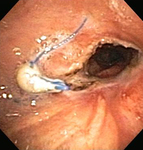

Бронхоскопическая терапия для обструкции нижних дыхательных путей правого главного бронха: аргоноплазменная коагуляция

Из коллекций Хосе Фернандо Сантакруза, дипломированного врача, члена Американской коллегии специалистов в области торакальной медицины, DAABIP, и Эрика Фолка, дипломированного врача, магистра наук; используется с разрешения